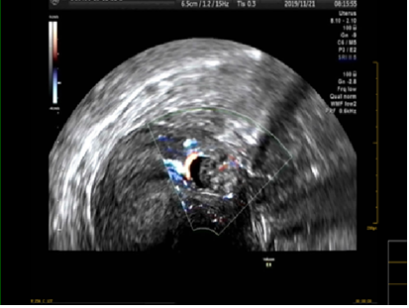

病例回顾:患者赵女士,31岁,有再生育要求。因“停经41天,阴道少量流血12天” 于2019年11月21日08时59分入院。患者既往有院外剖宫产手术史。入院前阴道超声提示:宫前壁切口处肌壁内查见一大小约2.0*32.5px的孕囊样回声,内未见卵黄囊及胚芽,CDFI显示周边可见较丰富血流信号,该处肌层菲薄,厚约3.75px。遂收住住院治疗。入院诊断:剖宫产术后子宫瘢痕妊娠(3型)。

该患者孕囊位于子宫切口处肌壁内,且该处肌层菲薄,厚约3.75px(如图1,2,3)。出血风险及子宫穿孔风险极大。为了保留生育功能,确保患者生命安全,我院妇科积极发起多学科联合诊疗(MDT)会议,特邀请放射科、麻醉科、超声科等相关科室开展讨论,一致决定先由放射科行子宫动脉栓塞术并灌注甲氨蝶呤杀胚治疗(微创介入),72小时之内再行清宫术。最终,该患者在放射科顺利完成甲氨蝶呤灌注和双侧子宫动脉栓塞(如图4-5)的情况下,第二天由妇科在超声科床旁监护下成功完成清宫术(如图6),宫腔镜检查宫腔及切口处无异常。术中出血仅有5ml(出血量较常规清宫术明显减少),并于术后第三天康复出院。

图3:切口妊娠-孕囊血流图像